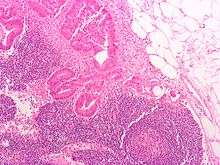

Section of small lymph node of rabbit.